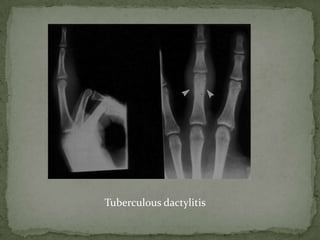

 Tubercular dactylitis

 primarily a disease of childhood

 affects short tubular bones distal to tarsus and wrist

 bones of the hands are more frequently affected than bones of

the feet

 proximal phalanx of the index and middle fingers and

metacarpals of the middle and ring fingers being the most

frequent locations

 Frequently present as marked swelling on the dorsum of the

hand and soft tissue abscess is normally a common feature

 Monostotic involvement is common

 Often follows a benign course without pyrexia and acute

inflammatory signs, as opposed to acute osteomyelitis.

 Plain radiography is the modality of choice for evaluation

and follow-up.

The radiographic features –

 Cystic expansion of the short tubular bones have led to the

name of "spina ventosa" being given to tubercular dactylitis

of the short bones of the hand.

 spina - short bone and

 ventosa - expanded with air

 Bone destruction and fusiform expansion of the bone

 It is most marked in diaphysis of metacarpals and metatarsals

in children

 Periosteal reaction and sequestra are uncommon.

 Healing is gradual by sclerosis.

 Spina ventosa

Tuberculous dactylitis